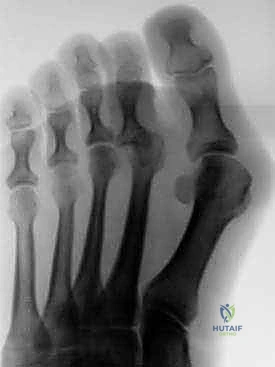

تشوهات أصابع القدم الصغيرة: دليل شامل للعلاج الجراحي وغير الجراحي مع الأستاذ الدكتور محمد هطيف في صنعاء

هل تعاني من آلام وتشوهات أصابع القدم الصغيرة؟ يقدم الأستاذ الدكتور محمد هطيف في صنعاء أحدث طرق التشخيص والعلاج الجراحي وغير الجراحي لتصحيح …